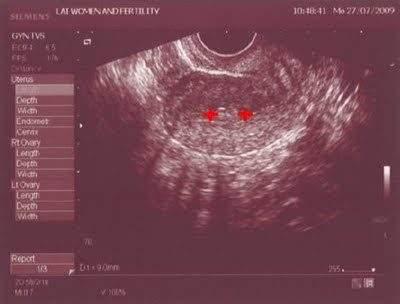

Jul 27, 2009

It was day 14 of my menses; my appointment with the gynecologist again. This time, I had 2 issues. First was that my menses came a week earlier than it was supposed to and secondly, it last a week longer than my normal menses. It was day 14 and yet, I was still bleeding. Thus, when the doc told me that it was still there and that it has to be surgically removed, it didn't come as a big surprise.